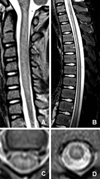

This review highlights clinical features of the increasing cases of acute flaccid paralysis associated with anterior myelitis noted in the United States from 2012 to 2015. Acute flaccid myelitis refers to acute flaccid limb weakness with spinal cord gray matter lesions on imaging or evidence of spinal cord motor neuron injury on electrodiagnostic testing. Although some individuals demonstrated improvement in motor weakness and functional deficits, most have residual weakness a year or more after onset. Epidemiological evidence and biological plausibility support an association between enterovirus D68 and the recent increase in acute flaccid myelitis cases in the United States. Ann Neurol 2016;80:326-338.